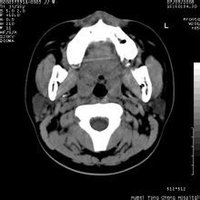

鼻咽部ct軸位平掃(層厚、層距均為5mm),圖像如下:

顳窩纖維血管瘤